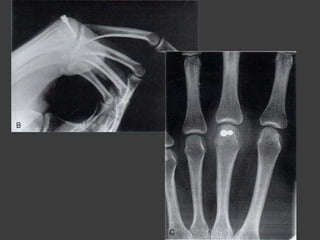

Fx de la cabeza de los

metacarpianos

Fijación de fragmento grandes -

anterogrado

Fijación de fragmentos

pequeños - retrogrado

Fx del cuello de los

 Trauma directo con mano empuñada

 Fx del boxeador

 Fx impactada hacia volar con

angulación dorsal

 Angulación severa…. Dedo en garra

 Angulación tolerada:

- 2-3° MC:…..15°

- 4° MC:……..35°

- 5° MC:………45 (incluso hasta 60°)